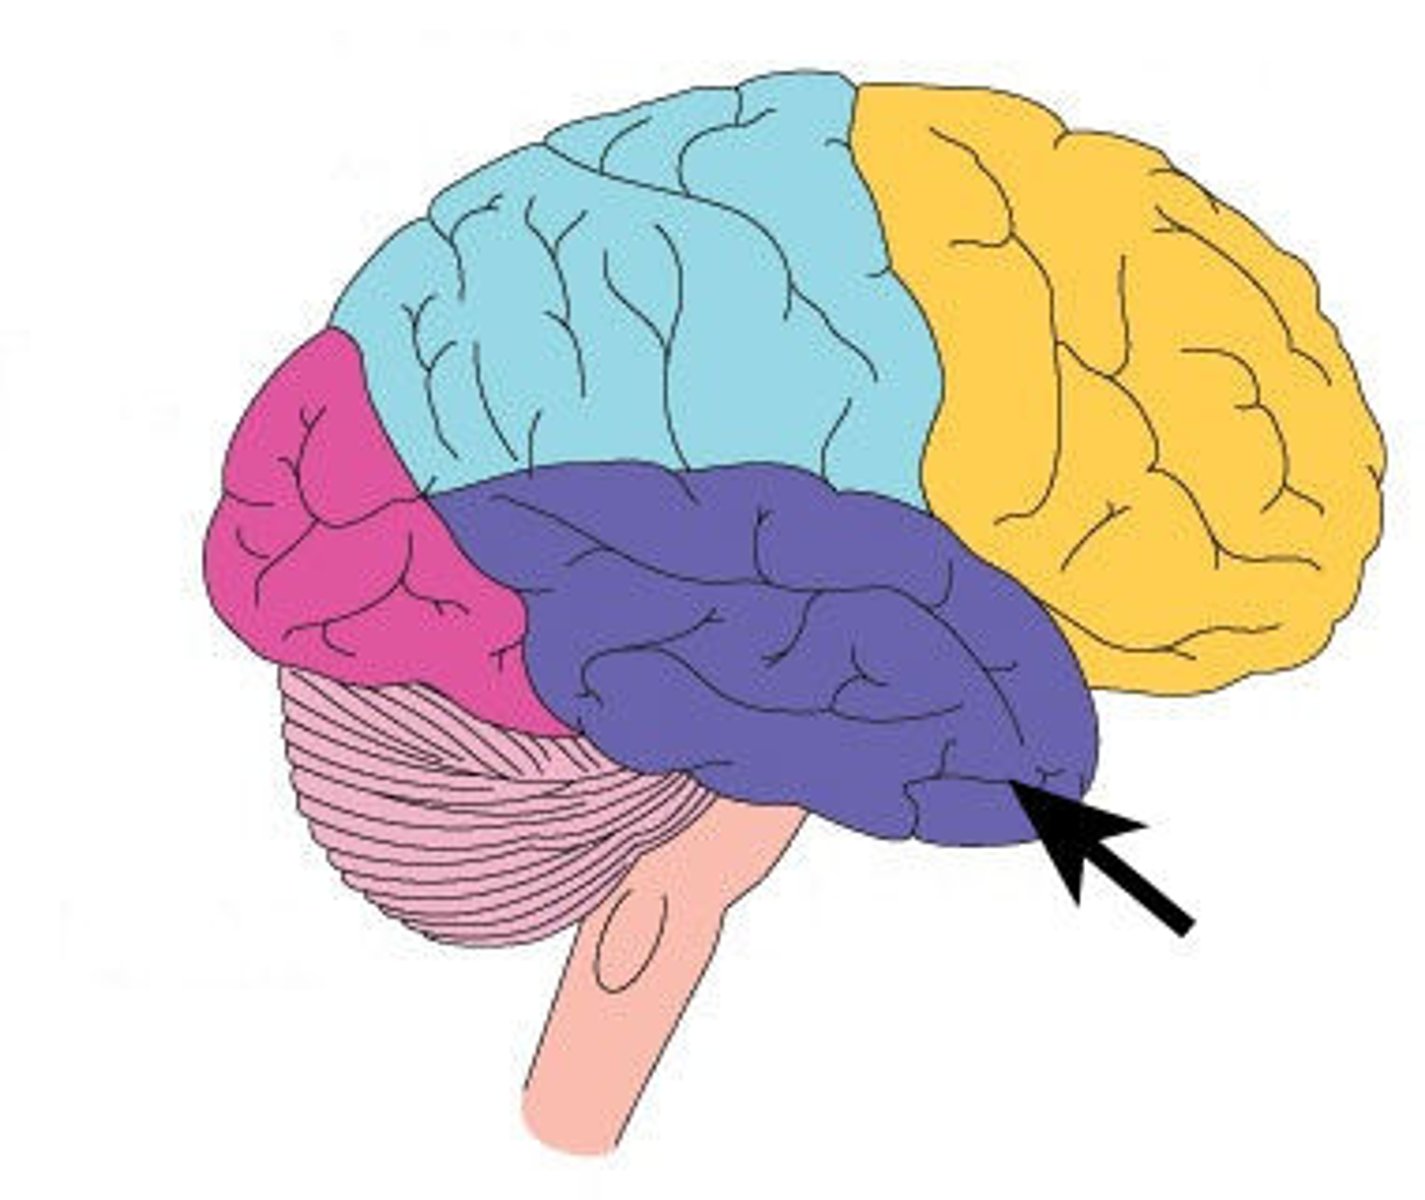

temporal lobe

occipital lobe